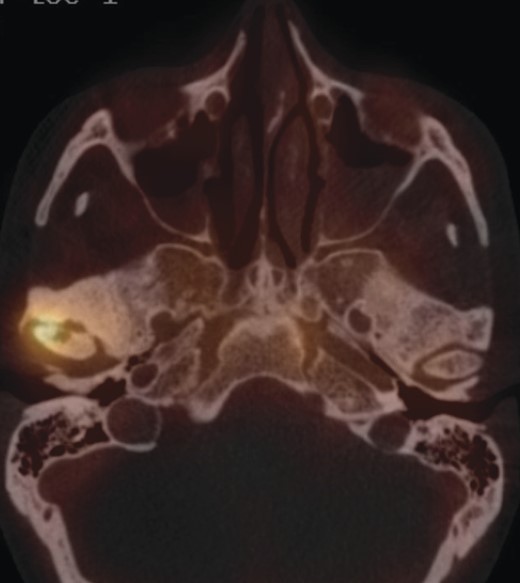

Approximately 4 months later symptoms returned. A computed tomography (CT) scan of the head was ordered by the oncologist. An osteolytic lesion and partial sclerosis of the right condylar head and neck were found, as well as effusion in the right TMJ (Fig. 1). The signs were interpreted as arthritis of the TMJ.

CT scan of the head (coronal section), arrow indicates osteolysis of the right condylar head.